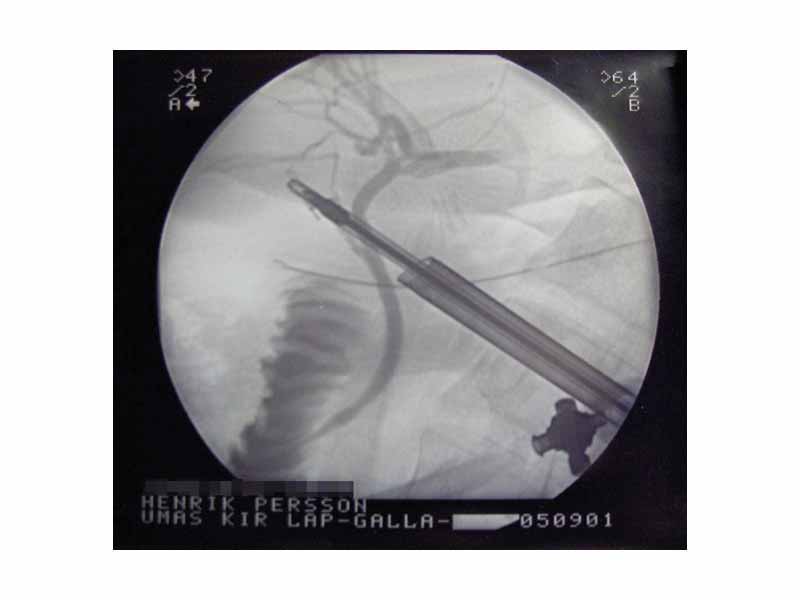

X-ray during Cholecystectomy